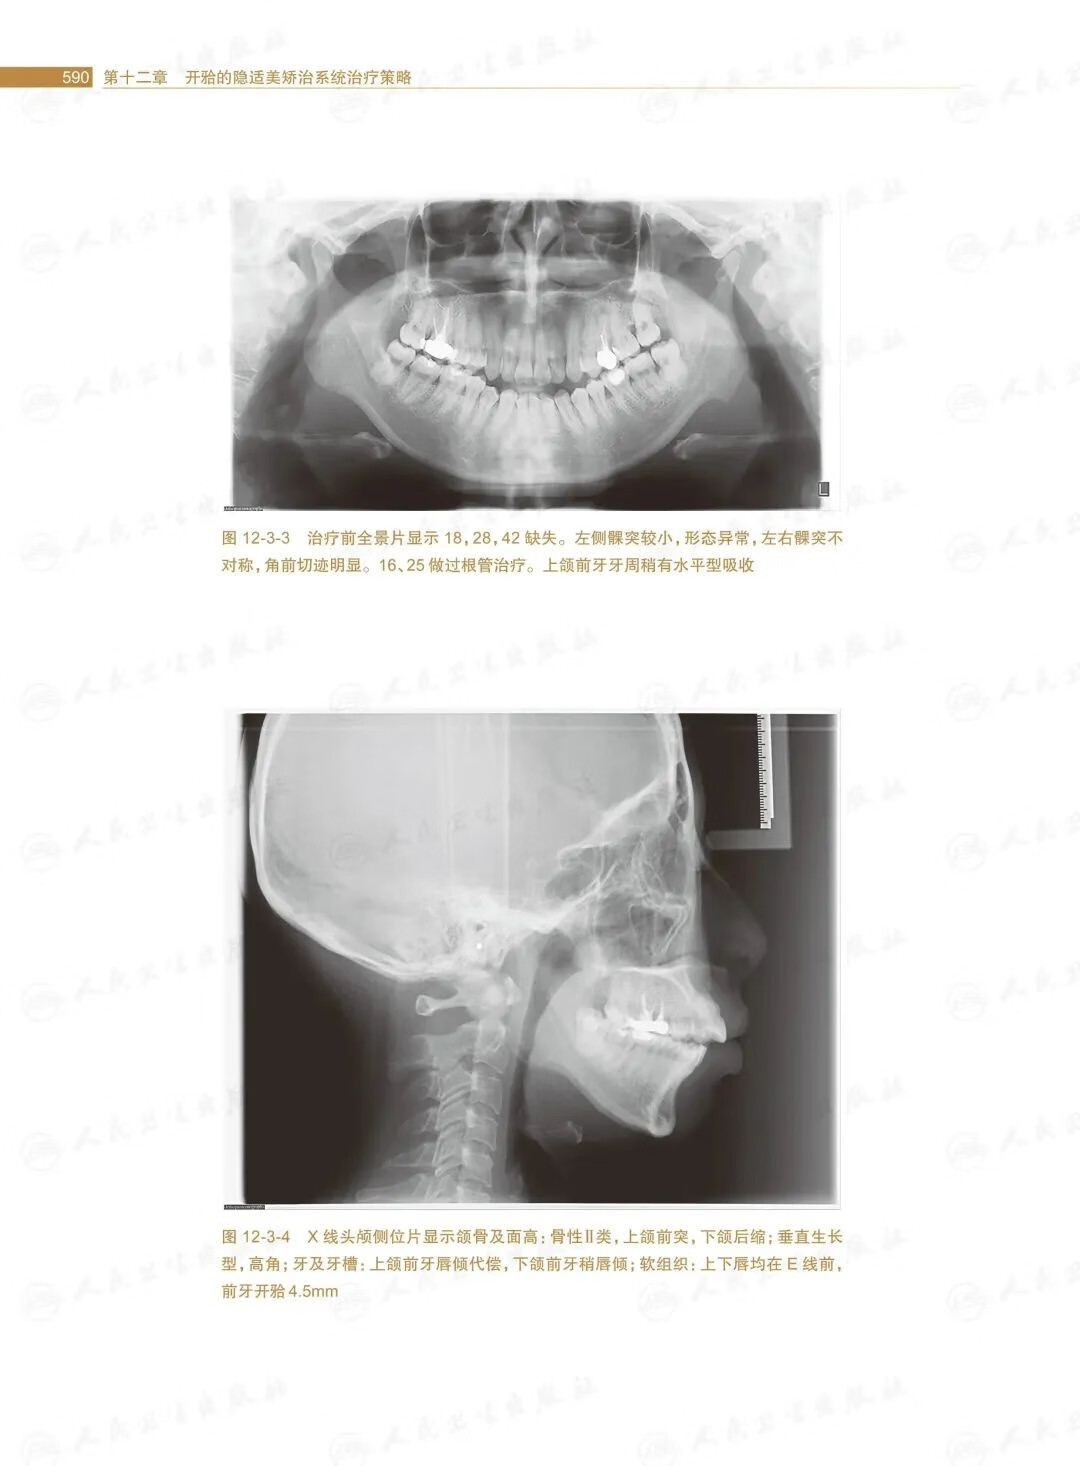

第十二章開的隱適美矯治系統治療策略/.569

第三節安氏Ⅱ類開的矯治策略/588